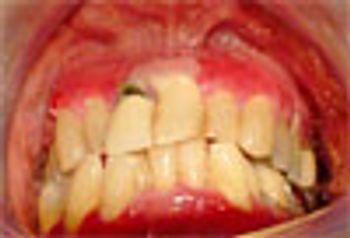

Benign mucous membrane pemphigoid is an autoimmune disease; that involves the oral mucosa and eyes. Clinical signs: edematous bright red gingiva and bullae formation.